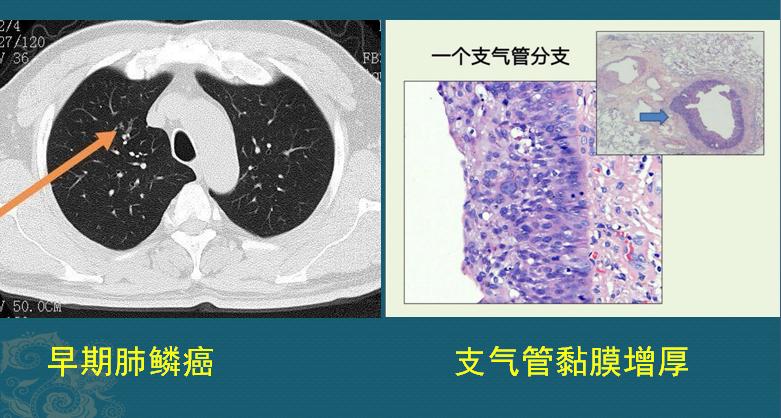

病例1,早期肺鳞癌,周围型:

这位病人是55岁男子,因为咳嗽就诊,是癌细胞刺激气道黏膜感受器所致,CT发现右肺上叶一处支气管壁增厚,支气管镜找到鳞癌细胞,没有突破基底膜,早期根治了。

这些管道内面,覆盖一层柔软的黏膜,我们把一根支气管横着切开,放到显微镜下放大,最内层的一圈紫色线状结构就是黏膜层(肺鳞癌就发生于此处):